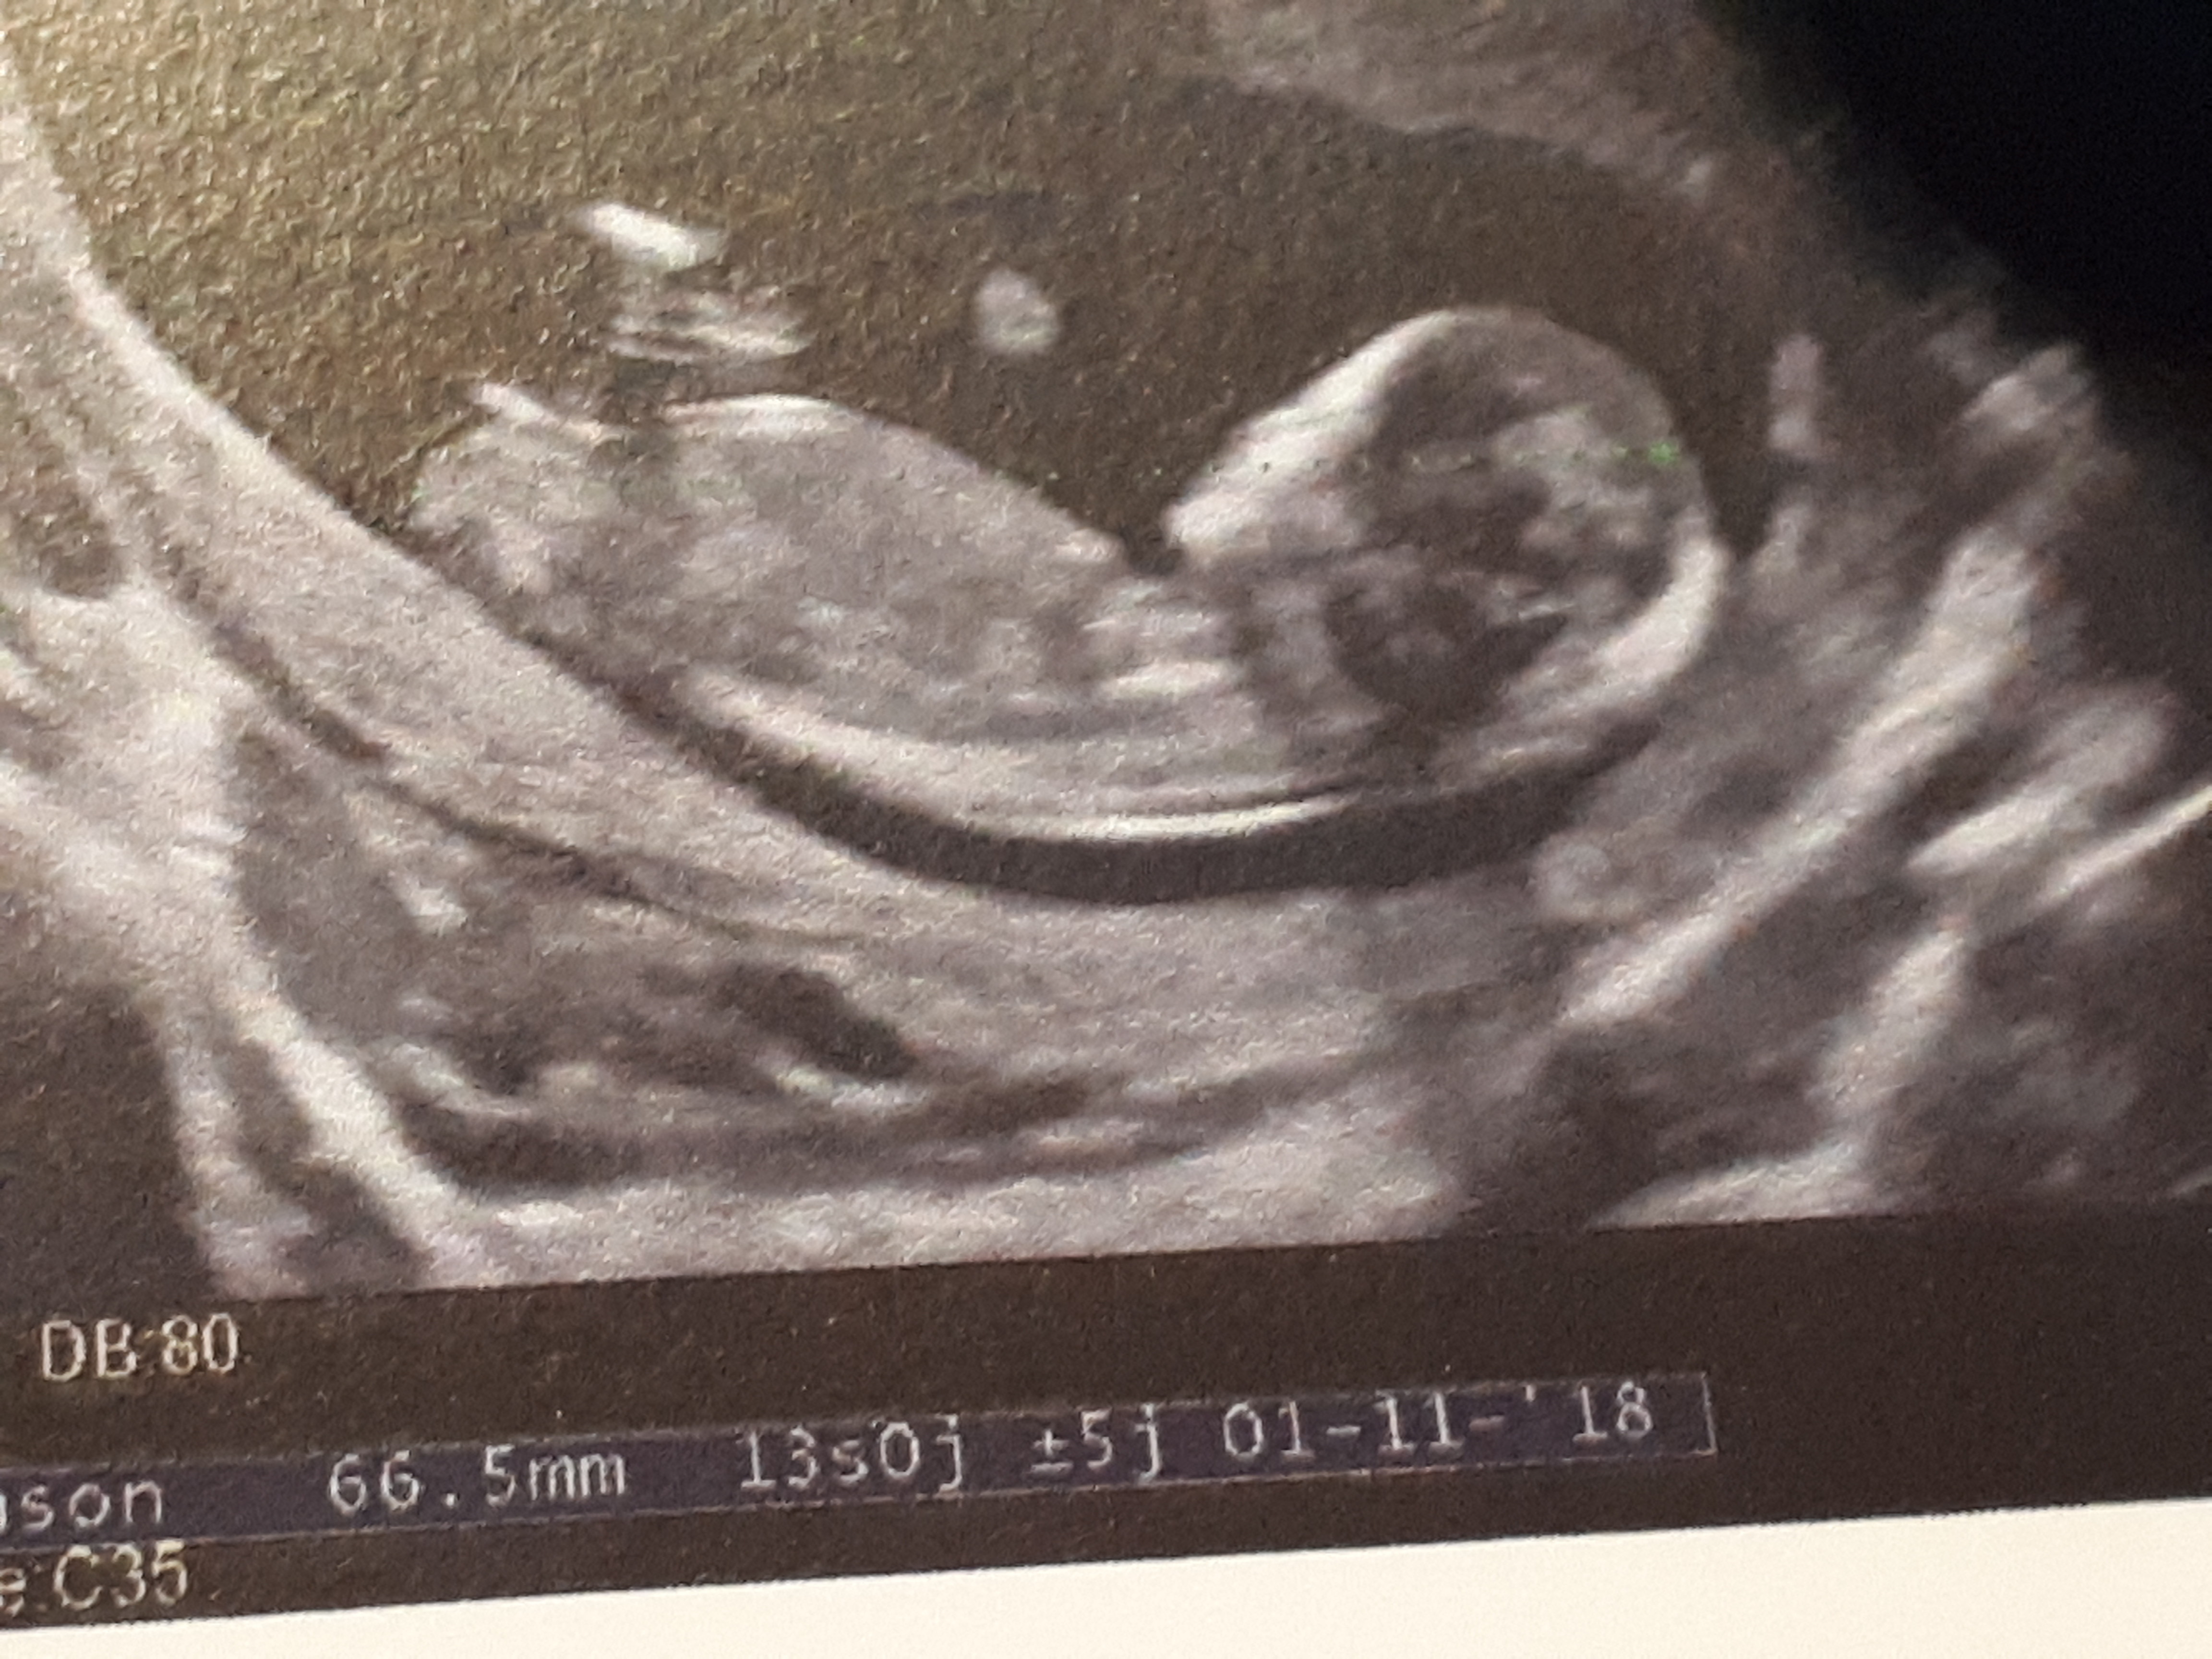

A 33 semaine de grossesse, soit au 8ème mois, le bébéLa Lcc est de 66 mm a 13 semaines d aménorrhée plus 6 Cordialement Répondre Hourdiaux 28 février 17, 22 h 13 min Bjr, merci par avance C est ma deuxième grossesse et j ai eu un garçon La Lcc est de 66 mm a 13 semaines d aménorrhée plus 6 j aurai voulu votre avis , je n arrive pas àDécouvrez nos conseils pour que cette transition se passe au mieux En bonus nos exercices de fitness pour retrouver votre silhouette

Semaine 13 de grossesse 15 SA Treize, un nombre portebonheur et si on croit les femmes enceintes, c'est le cas La grossesse ne rime plus avec tracas quotidiens La femme enceinte de treize semaines retrouve sa vitalitéPossède environ 13 milliards de connexions !En cette 15ème semaine d'aménorrhée, la future maman doit donc prendre soin de sa peau Une crème antivergeture peut être appliquée

A 13 semaines de grossesse, ou 15 semaines d'aménorrhée, votre bébé8), 3ème mois (semaine 9 àDu cerveau, le bébé